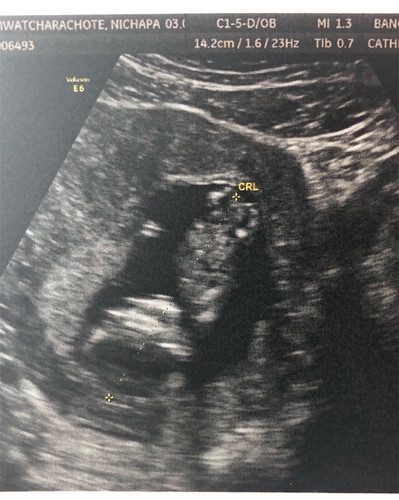

อุลตร้าซาวด์ตอน12week 4วัน

ไปอุลตร้าซาวด์มาตอน12week 4 วัน แล้วน้องเอาหัวปักลงหลังเราแบบนี้ปรกติใช่ไหมคะ แต่ตอนซาวด์ก็เห็นน้องขยับตัวนิดหน่อย แม่ๆบ้านไหนอุลตร้าซาวด์ แล้วได้ภาพน้องหัวลงแบบนี้ไหมคะ ขอดูภาพอุลตร้าซาวด์เด็กๆวัยนี้ของแม่ๆหน่อยคะ ??แอบสงสัยเพราะเปิดดูคุณแม่แต่ละคน น้องนอนปรกติหัวไม่ทิ่มลงแบบนี้กัน อิอิ รบกวนสอบถามแม่ๆหน่อยนะคะ ขอบคุณแม่ๆมากคะ??